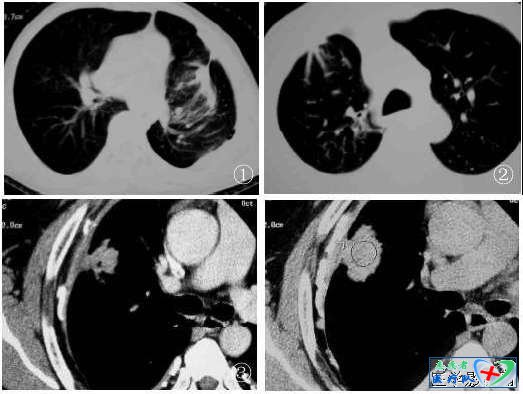

12、棘状突起征(棘突征、锯齿征伪足征):

指结节边缘呈尖角状突起,如同小的三角形,使病灶边缘不规则。如果棘状突起密集排列就构成了“锯齿征”;如果棘状突起粗细、长短不一时,如螃蟹足,就是“伪足征”。上述三种征象其实都是棘突征的不同表现,是介于分叶和毛刺之间的的一种粗大而钝的结构。其病理基础是肿瘤发育先端的浸润性生长,肿瘤因子诱发肿瘤新生血管致使肿瘤组织生长速度不均匀,尤其肿瘤周边部的血管丰富、密度大、数量多(主要来源于支气管动脉,少数来自肺动脉及其他侧枝血管),因而癌细胞增殖活跃;其次,邻近肺组织的瘤巢或肿瘤浸润,使结缔组织水肿、纤维化、增厚等形成棘状突起;第三,肿瘤周围的生长环境如小叶间隔或血管等组织的阻挡作用;另外一种情况是肿瘤突出部分与CT扫描层面部分相切而成尖角状改变。棘状突起也是分叶征的一部分,因此,棘状突起也是肺癌的的重要征象。